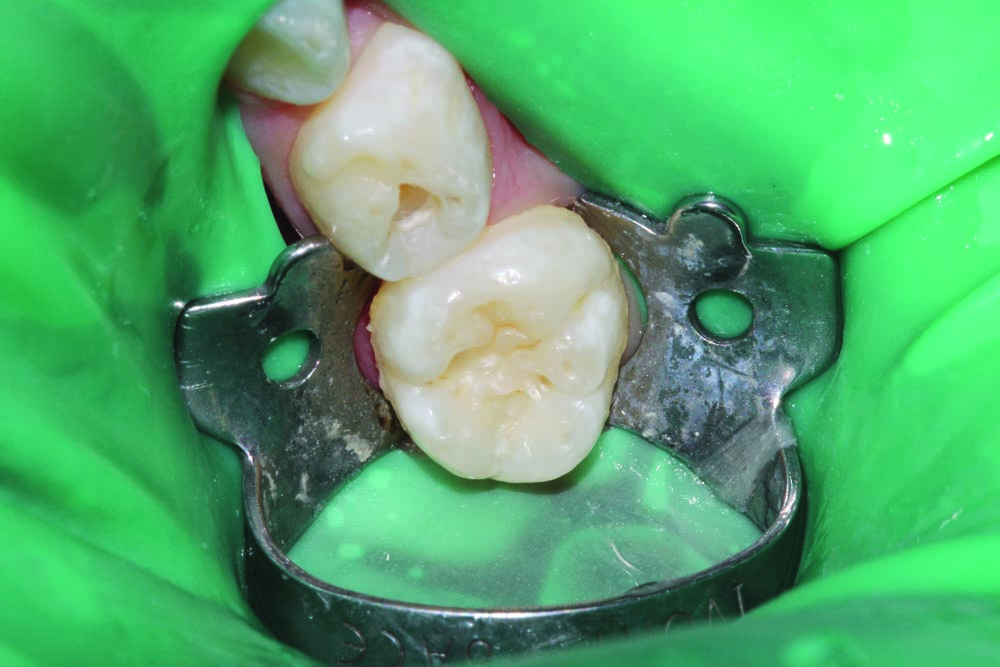

A 3-year-old patient presented with multiple carious lesions in all quadrants. Dental restorations were carried out with patient under general anesthetic. Quadrant 4, teeth #84 (S) and #85 (T) each were cavitated on the occlusal surface into dentin (Fig. 1).

The quadrant was isolated with an 8A ivory clamp and slot-style rubber dam, and a conservative outline was prepared using an NSK high-speed handpiece and a 330 FG bur. Caries was excavated with an NSK slow-speed handpiece and 6 and 8 round burs (Fig. 2) followed by a selective-etch technique with phosphoric acid (Fig. 3).

Futurabond U was applied to the preparation and the entire occlusal surface (Fig. 4). Teeth were restored with Admira Fusion by Voco, an all-ceramic-based universal restorative material, then shaped and light-cured before a final layer of Admira Fusion Flow was placed over the entire occlusal surface to act as a sealant for any additional pits and fissures on the occlusal surface, as seen in the final completed restorations (Fig. 5).

• Figure 1

• Figure 2